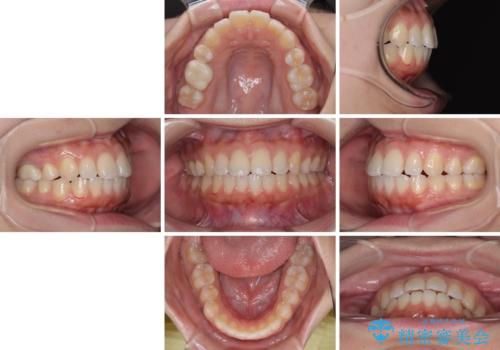

再矯正 開咬に後戻りした歯列をインビザラインで改善

インビザラインは前歯部の開咬に効果的であることが多く、ライトパッケージにもかかわらず、十分満足のいく仕上がりとなりました。